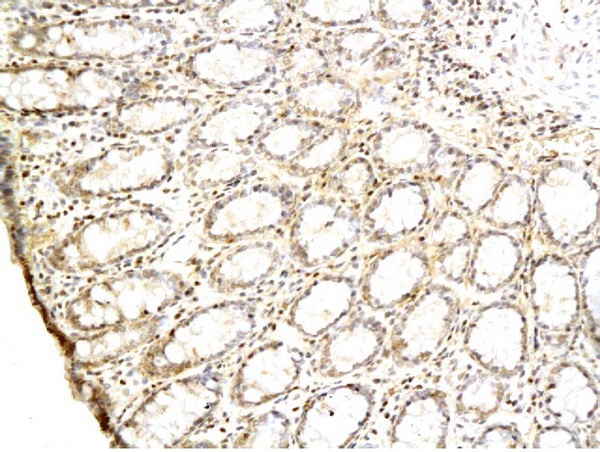

TGF alpha Polyclonal Antibody

Product Name TGF alpha Polyclonal Antibody

Background TGF alpha is a mitogenic polypeptide that is able to bind to the EGF receptor/EGFR and to act synergistically with TGF beta to promote anchorage-independent cell proliferation in soft agar.